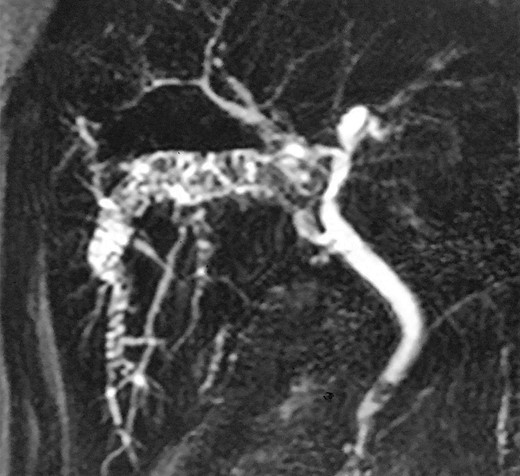

Physical examination revealed right hypochondrial tenderness but was otherwise unremarkable. Laboratory investigation revealed normal bilirubin, aspartate aminotransferase, and alanine aminotransferase, and gamma-glutamyl transpeptidase of 550 U/L (normal up to 50 U/L) and alkaline phosphatase of 350 U/L (normal up to 120 U/L). Abdominal ultrasound revealed a dilated intrahepatic duct with stones, but no extrahepatic stone was observed. Abdominal computed tomography showed stones within a dilated intrahepatic bile duct of segment 6 and a small radiopaque image with metallic density (Fig. 1). Magnetic resonance cholangiopancreatography (MRCP) revealed a dilated intrahepatic bile duct of segment 6 filled with stones. A single filling defect in the distal common bile duct was also observed (Fig. 2). The case was discussed at a hepatobiliary meeting. Due to the difficult position of the stones (segment 6), endoscopic retrograde cholangiopancreatography was not possible and liver resection was indicated. The patient underwent surgery after preoperative evaluation.